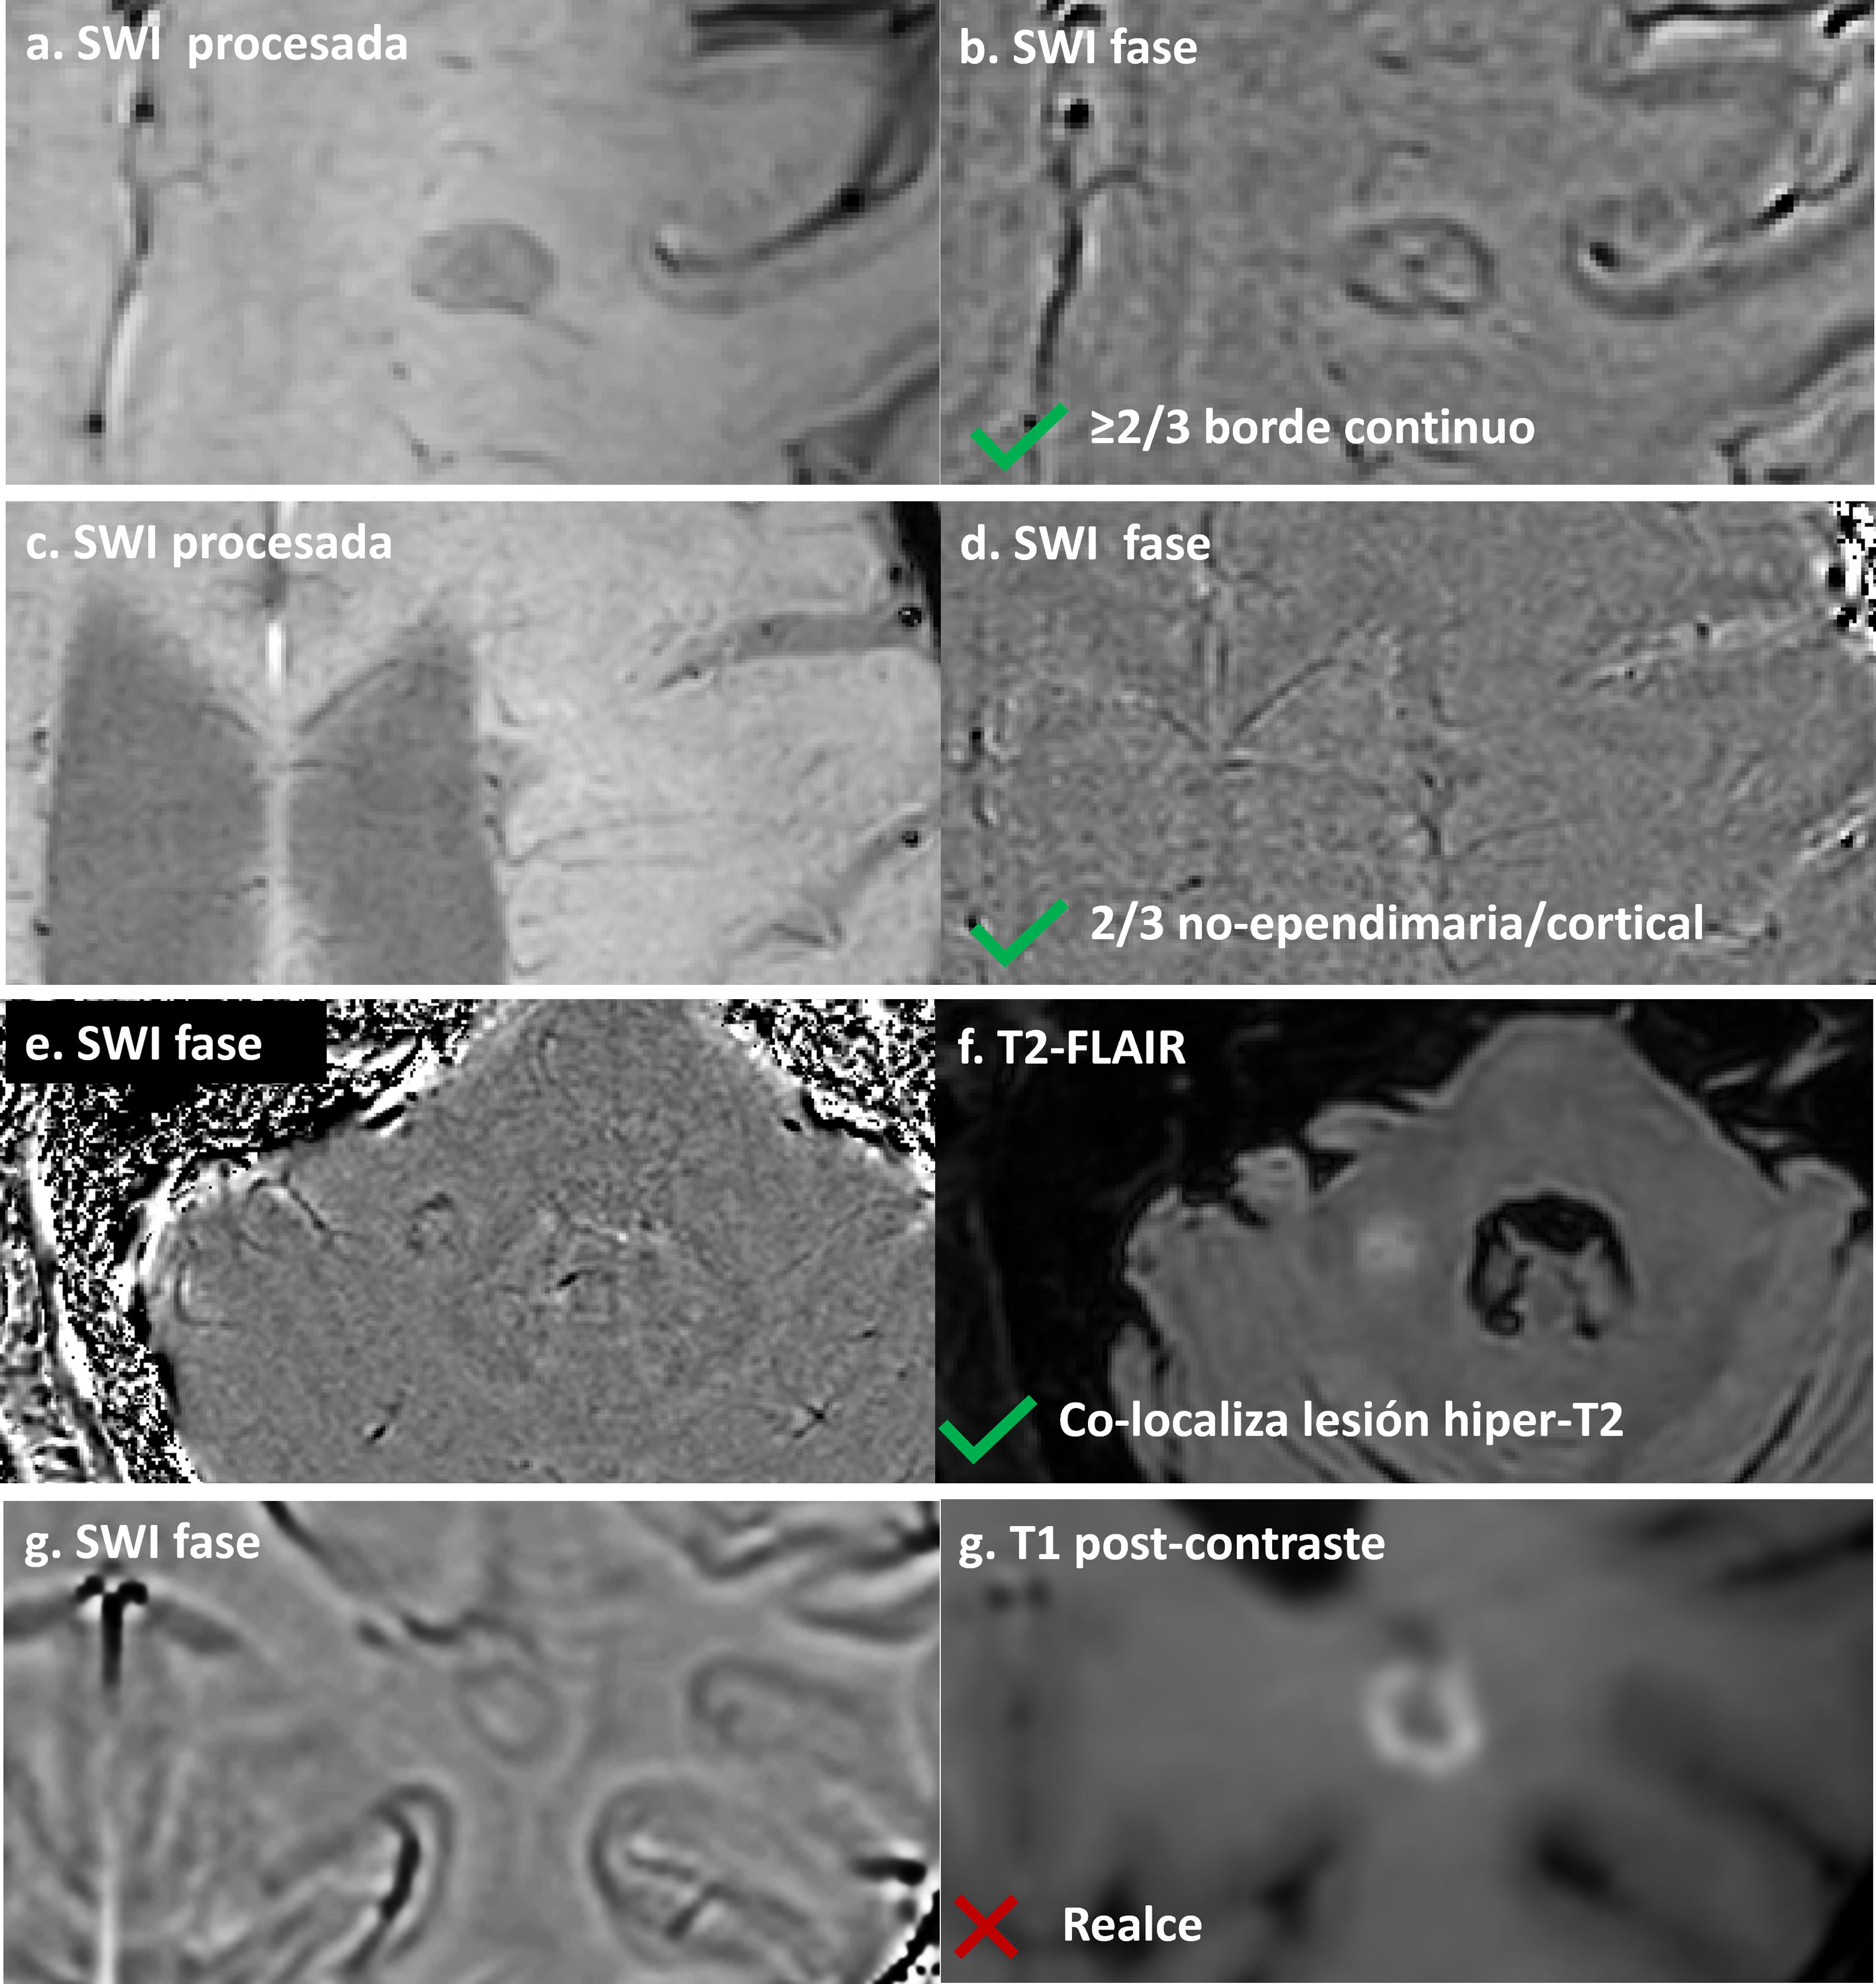

El consenso NAIMS de 2024 define una PRL como una lesión que demuestra un borde discreto con propiedades paramagnéticas sobre secuencias sensibles a la susceptibilidad, continua a lo largo de al menos dos tercios del borde externo de la porción de sustancia blanca de la lesión, co-localizada con un núcleo de lesión T2-hiperintenso y no captante, y visible en al menos dos cortes consecutivos o en dos planos ortogonales30. La definición completa, incluidos los criterios de exclusión, se proporciona en la tabla 2 e ilustrado en la figura 3.

Identificación de lesiones con borde paramagnético. (a, b) SWI procesada (a) e imagen de fase (b) que muestran una lesión con borde paramagnético continuo a lo largo de más de dos tercios del perímetro, cumpliendo criterios de PRL. (c, d) Lesión periventricular en SWI (c) y fase (d) con borde continuo a través de todo el borde de la sustancia blanca; el borde ependimario (flecha) queda excluido de la evaluación según el consenso NAIMS. (e, f) Imagen de fase (e) y T2-FLAIR (f) que demuestran la colocalización necesaria del borde paramagnético con un núcleo de lesión hiperintenso en T2. (g, h) Criterio de exclusión: imagen de fase (g) muestra un borde hipointenso en una lesión con realce anular en T1 post-gadolinio (h). Las lesiones captantes deben excluirse de la clasificación PRL.

Consideraciones prácticas. La identificación de PRL requiere experiencia técnica y protocolos optimizados. Dada la complejidad y dependencia de la intensidad de campo de 3T, las PRL deben interpretarse con precaución, especialmente en centros sin amplia experiencia; por ello, los criterios de 2024 asignan a las PRL un papel diagnóstico más limitado que el del CVS. La detección de PRL requiere secuencias de ecos de gradiente con reconstrucción de imagen de fase. Aunque las reconstrucciones tipo SWI son aceptables, se recomiendan mapas de fase para una visualización óptima del borde30. La detección es más fiable a 3T, aunque factible a 1,5T con protocolos optimizados32. Los principales riesgos interpretativos incluyen venas que corren junto a los bordes de la lesión, que pueden imitar un borde paramagnético. Las lesiones captantes deben excluirse, ya que el borde paramagnético refleja inflamación crónica—no aguda—. Se ha descrito una fiabilidad entre evaluadores del 90–97% en centros experimentados, aunque el acuerdo puede ser menor en entornos no expertos30.